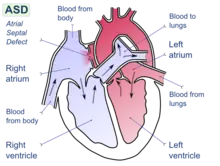

| Illustration of an atrial septal defect. | |

Atrial septal defect (ASD) is a congenital heart defect in which blood flows between the atria (upper chambers) of the heart. Some flow is a normal condition both pre-birth and immediately post-birth via the foramen ovale; however, when this does not naturally close after birth it is referred to as a patent (open) foramen ovale (PFO). It is common in patients with a congenital atrial septal aneurysm (ASA).

After PFO closure the atria normally are separated by a dividing wall, the interatrial septum. If this septum is defective or absent, then oxygen-rich blood can flow directly from the left side of the heart to mix with the oxygen-poor blood in the right side of the heart; or the opposite, depending on whether the left or right atrium has the higher blood pressure.[1] In the absence of other heart defects, the left atrium has the higher pressure. This can lead to lower-than-normal oxygen levels in the arterial blood that supplies the brain, organs, and tissues. However, an ASD may not produce noticeable signs or symptoms, especially if the defect is small. Also, in terms of health risks, people who have had a cryptogenic stroke are more likely to have a PFO than the general population.[2]

A cardiac shunt is the presence of a net flow of blood through a defect, either from left to right or right to left. The amount of shunting present, if any, determines the hemodynamic significance of the ASD. A right-to-left-shunt results in venous blood entering the left side of the heart and into the arterial circulation without passing through the pulmonary circulation to be oxygenated. This may result in the clinical finding of cyanosis, the presence of bluish-colored skin, especially of the lips and under the nails.